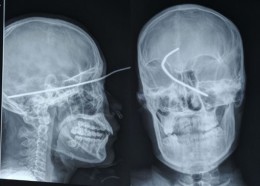

Чудни ренгенски снимки

Фото на денот #630